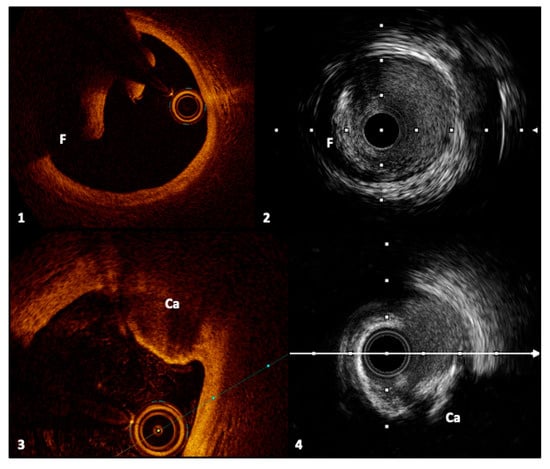

4.3. Calcified Lesions

- Mintz, G.S. Intravascular imaging of coronary calcification and its clinical implications. JACC Cardiovasc. Imaging 2015, 8, 461–471. [Google Scholar] [CrossRef]

- Wang, X.; Matsumura, M.; Mintz, G.S.; Lee, T.; Zhang, W.; Cao, Y.; Fujino, A.; Lin, Y.; Usui, E.; Kanaji, Y.; et al. In Vivo Calcium Detection by Comparing Optical Coherence Tomography, Intravascular Ultrasound, and Angiography. JACC Cardiovasc. Imaging J. 2017, 10, 8. [Google Scholar] [CrossRef]